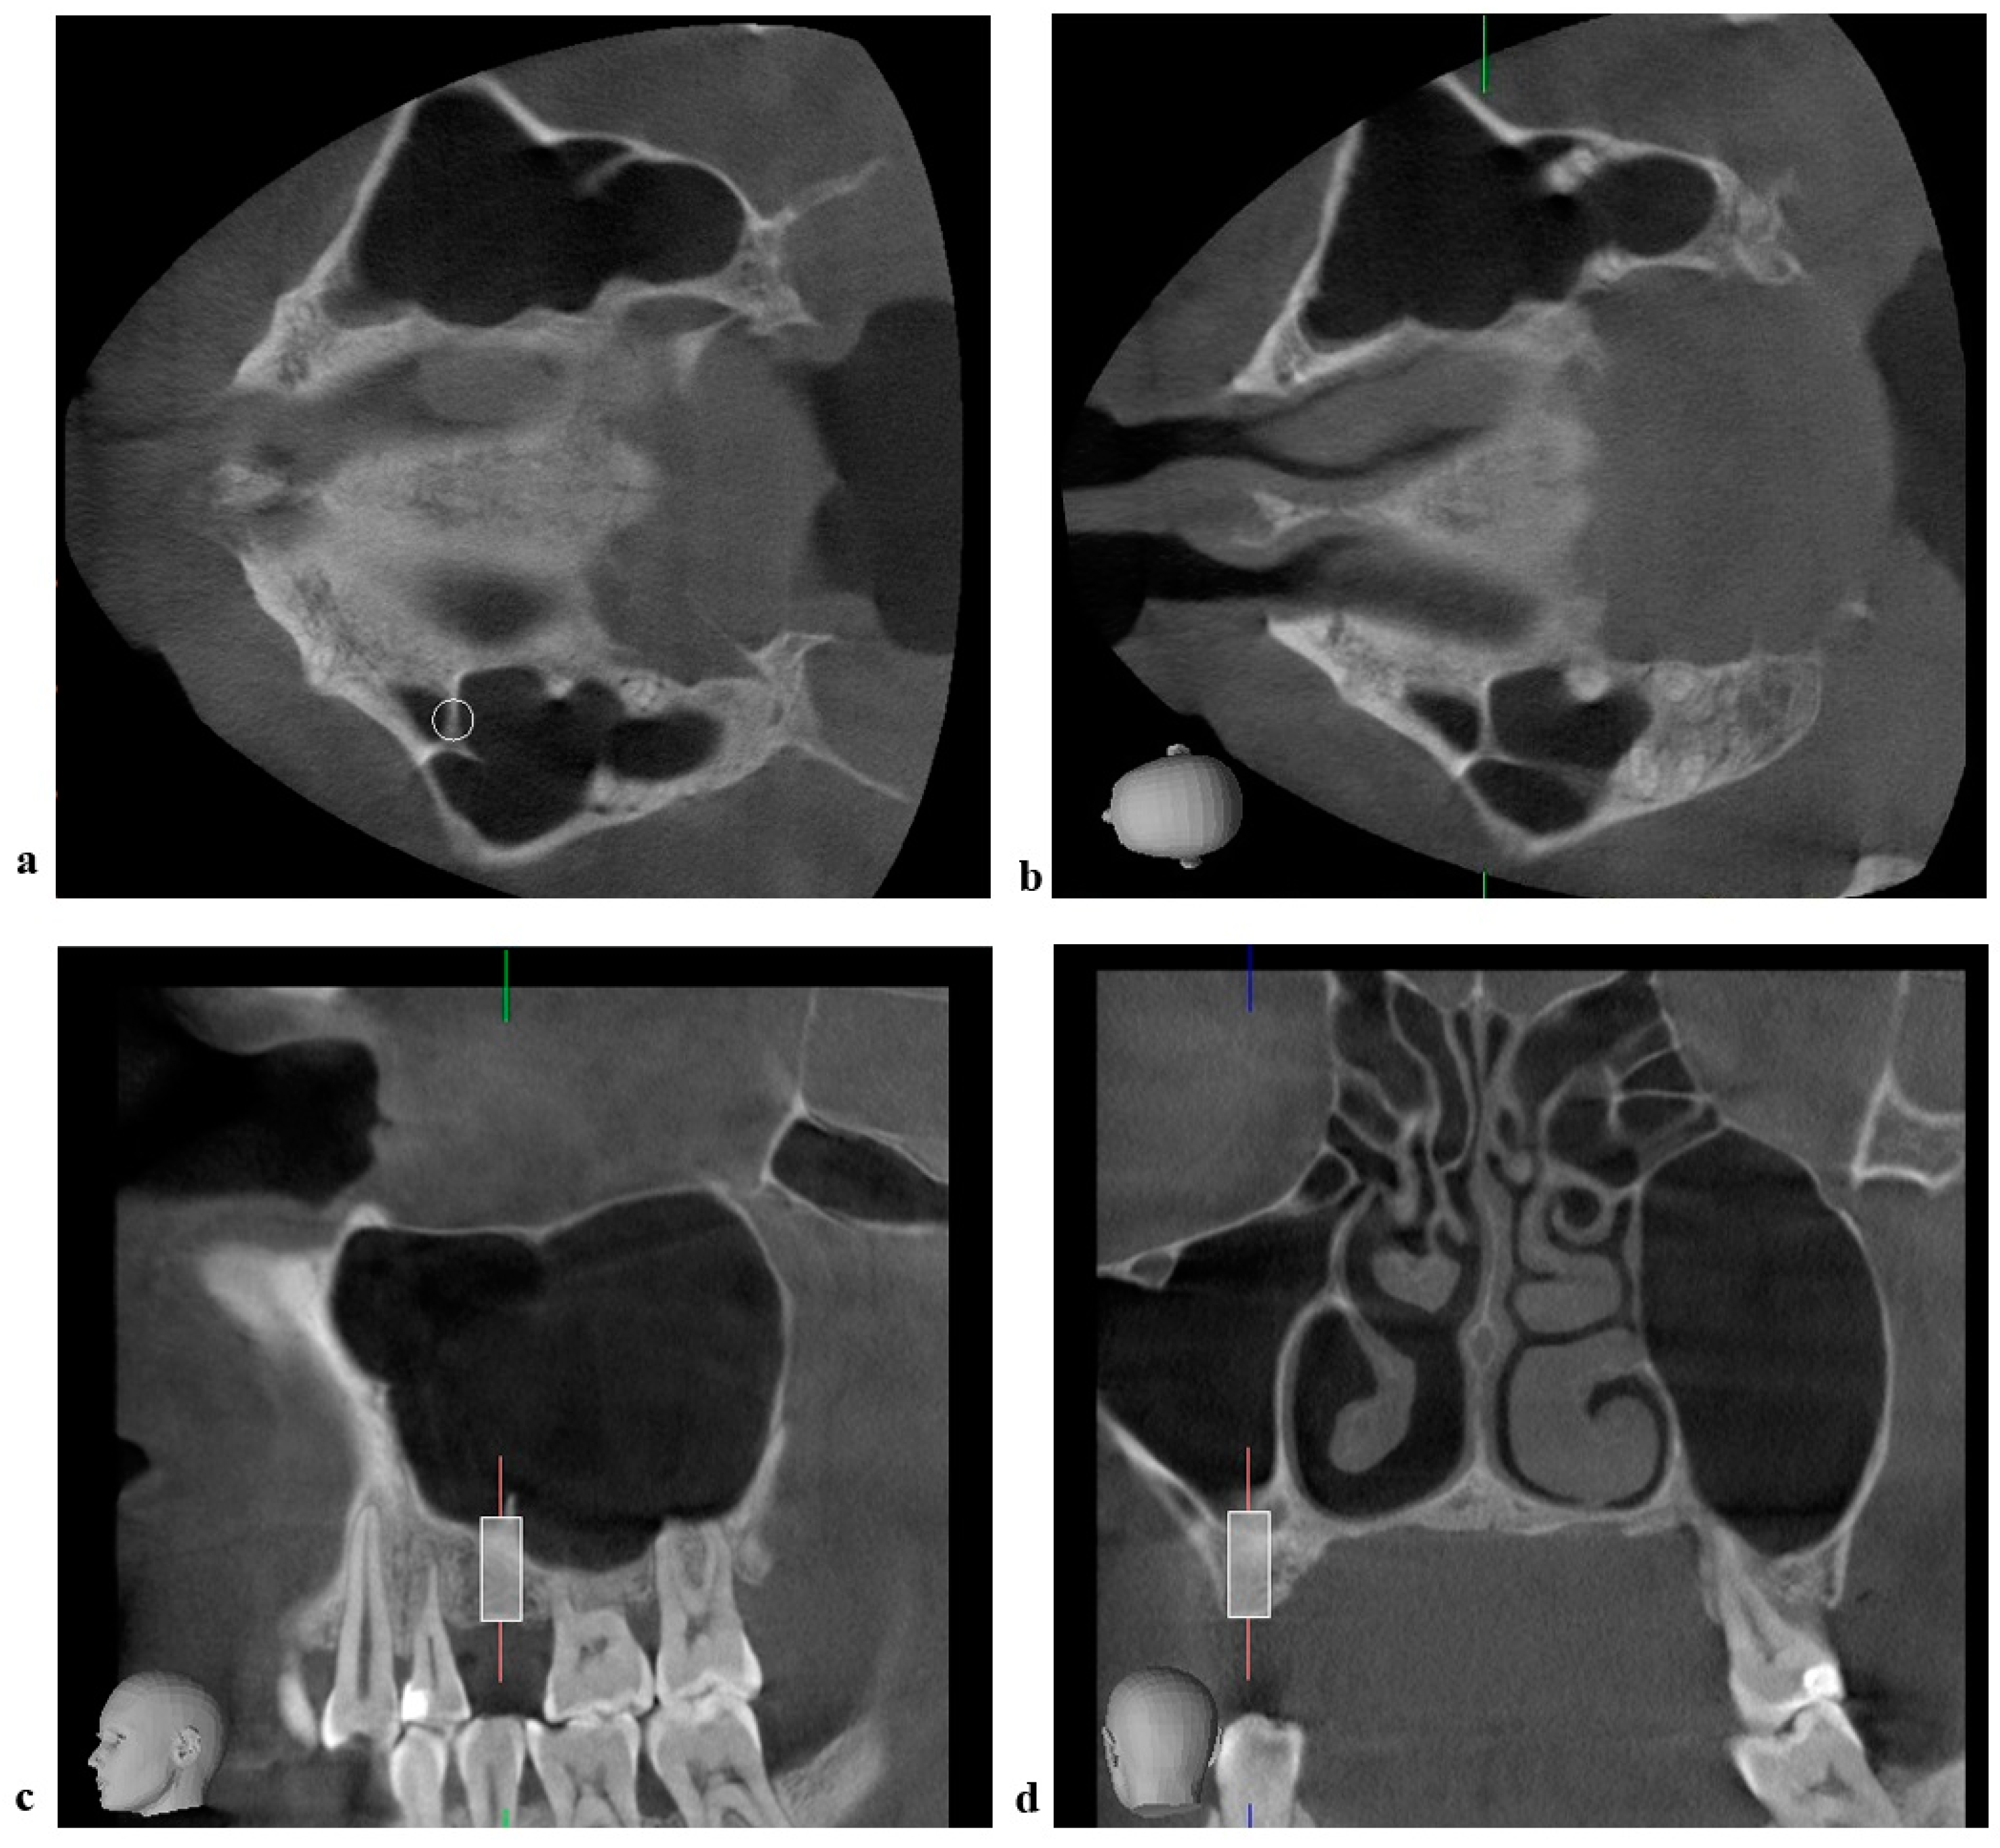

2.3. Radiographic Measurements

- Sigaroudi, A.K.; Kajan, Z.D.; Rastgar, S.; Asli, H.N. Frequency of different maxillary sinus septal patterns found on cone-beam computed tomography and predicting the associated risk of sinus membrane perforation during sinus lifting. Imaging Sci. Dent. 2017, 47, 261–267. [Google Scholar] [CrossRef] [PubMed] [Green Version]

- Jung, J.; Park, J.S.; Hong, S.J.; Kim, G.T.; Kwon, Y.D. Axial Triangle of the Maxillary Sinus, and its Surgical Implication With the Position of Maxillary Sinus Septa During Sinus Floor Elevation: A CBCT Analysis. J. Oral Implant. 2020, 46, 415–422. [Google Scholar] [CrossRef]

- Irinakis, T.; Dabuleanu, V.; Aldahlawi, S. Complications During Maxillary Sinus Augmentation Associated with Interfering Septa: A New Classification of Septa. Open Dent. J. 2017, 11, 140–150. [Google Scholar] [CrossRef] [PubMed] [Green Version]